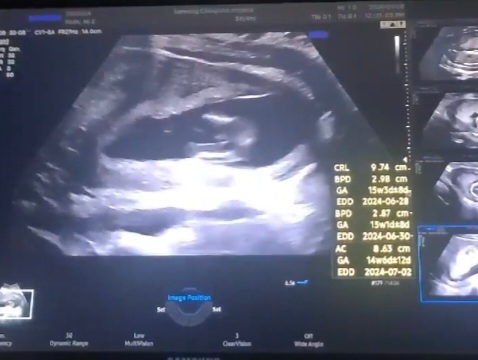

아들?ㅋㅋㅋ 뭔가 보이긴하는데 의사쌤은 14주엔 여자아이도 좀 튀어나오게 보일 수도 있다하셔서 아리까리하네요ㅋㅋ

저도 14주차에 아들 확인받고왔는데요 저희 아들이랑 똑같네여…ㅎㅎㅎ

그쵸..저도 아들같은데ㅋㅋ말끝을 흐리시더라구요ㅋㅋ성별언급하면 안돼서 그러셨나봅니당 크크